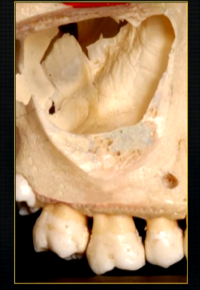

when the thin, surface bone of the maxilla is removed …

can see the roots of the teeth as they are positioned in the alveolar part of the maxilla

the alveolar bone has an internal trabecular, honeycomb appearance - wide enough to envelope all the roots of the posterior teeth

what is this thin line over the palate?

mid-palatal suture

what is this large hole?

naso-palatine foramen